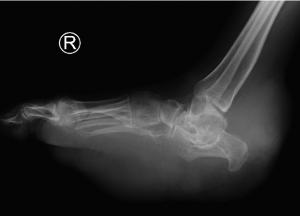

Figure 2

AP, Oblique and Lateral radiographs of the foot show multiple soft tissue densities specifically in the hindfoot (retrocalcaneal region) and the plantar aspect of the foot. In addition, there are erosions in the calcaneus, talus and midfoot.